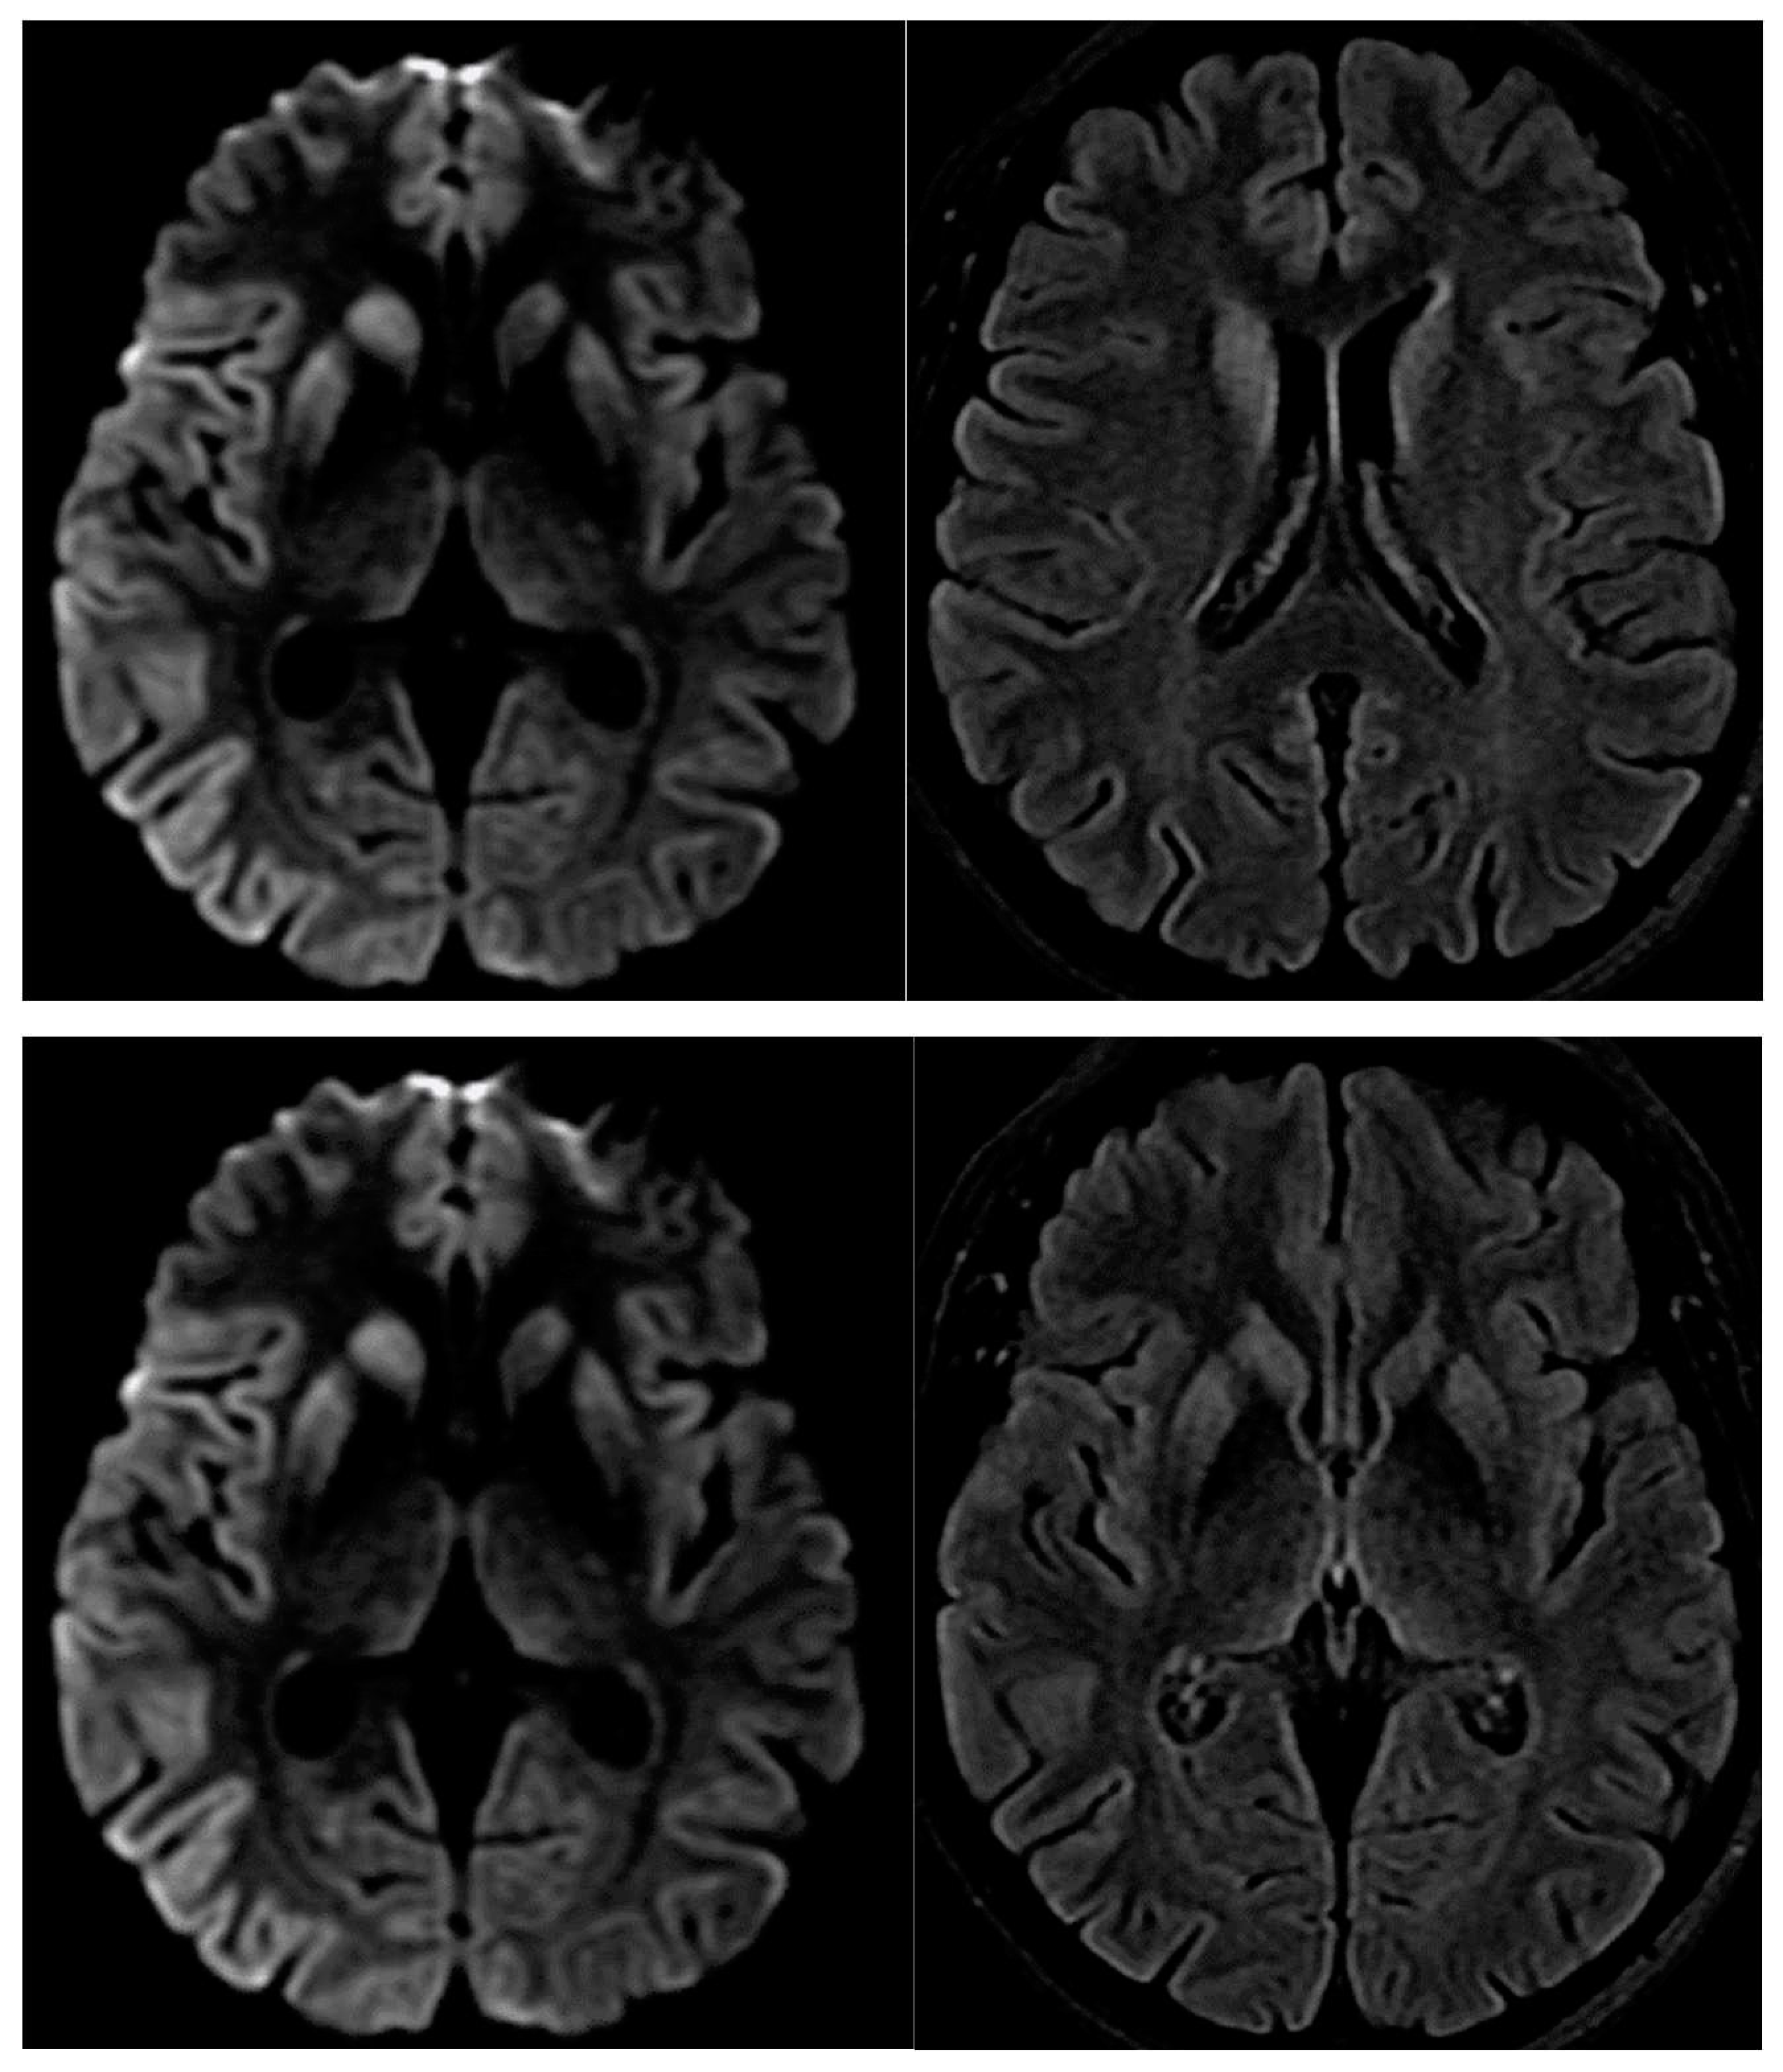

- Fulbright RK, Kingsley PB, Guo X, Hoffmann C, Kahana E, Chapman JC, Prohovnik I. The imaging appearance of Creutzfeldt-Jakob disease caused by the E200K mutation. Magn Reson Imaging. 2006;24(9):1121-9. [CrossRef]